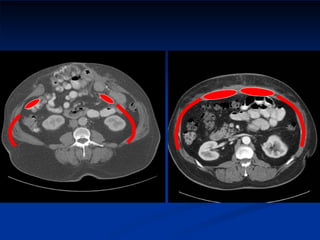

Port Site Recurrence